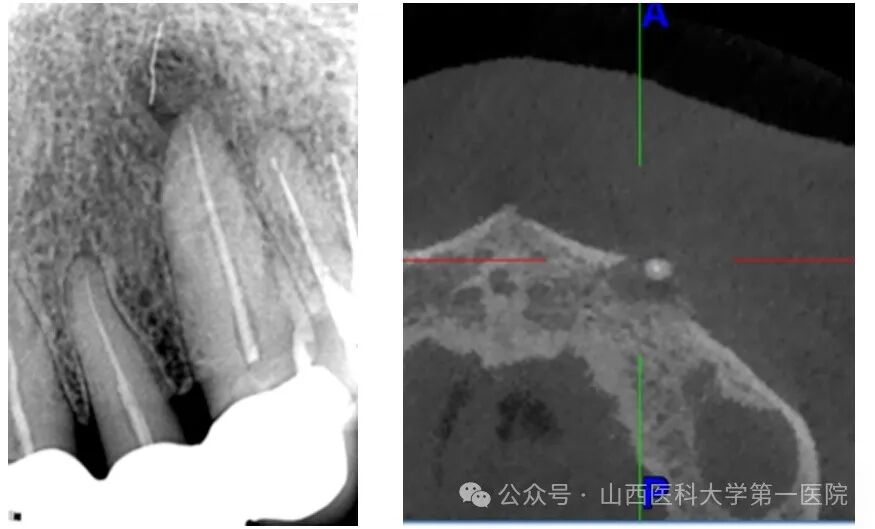

王女士4年前因牙痛在外院进行了左上前牙根管治疗及全冠修复,近1年来患牙再次出现肿痛、溢脓,且反复发作,严重影响生活质量,就诊于多家医院治疗方案都是拔除牙齿种植治疗或者去除牙冠进行再治疗,都不符合王女士保留牙冠的强烈意愿,她于是来到山西医科大学第一医院口腔内科进行诊治。孙晓军主任医师和车健医生接诊后,进行了详细的临床和影像学检查,发现患牙根尖周围有较大范围炎症,听取患者诉求后决定采取显微根尖手术,以达到不拆冠不拔牙实现保留患牙和美学效果。

医生术中采用牙龈翻瓣术清理根尖周围感染组织,同时对患牙进行倒预备倒充填严密封闭根尖,术后定期复查发现患者牙龈红肿明显消退,根尖炎症范围逐渐减小,1年后根尖炎症完全消失,成功保留了天然牙。